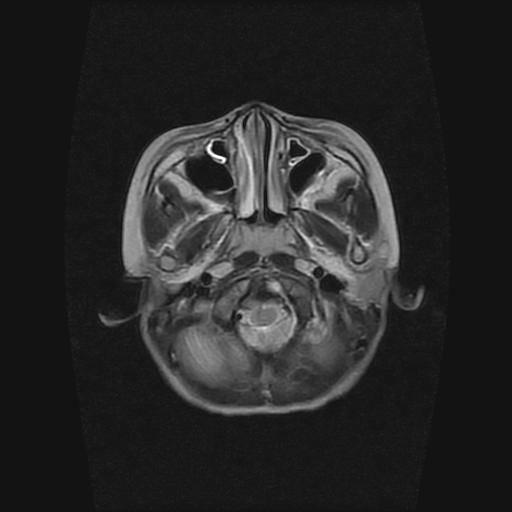

6岁小儿,左侧视神经瘤术后。现左侧视力减退。